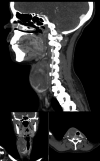

Case presentation: A 19-year-old pregnant woman presented with a rapidly enlarging right thyroid mass. Fine needle aspiration biopsy (FNAB) revealed a highly cellular, triphasic aspirate composed of primitive epithelium arranged in macrofollicular structures, spindled mesenchymal cells within a myxoid matrix, and small round blastemal cells. Immunocytochemistry showed TTF-1 and PAX8 positivity in epithelial cells, synaptophysin and SALL4 in blastemal cells, and myogenin in both spindled and blastemal components, supporting a cytological diagnosis of thyroblastoma. She underwent total thyroidectomy and neck dissection during the second trimester. Histology confirmed thyroblastoma with extensive lymph node metastases. Chemotherapy was initiated during pregnancy but discontinued due to neutropenic complications. She delivered a healthy infant and remained disease-free at her 12-month follow-up.